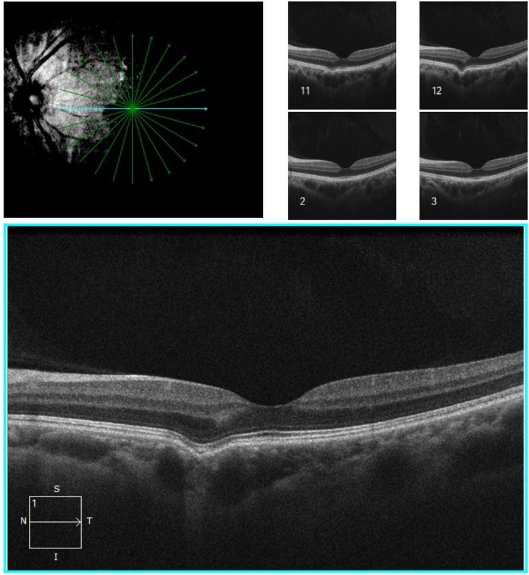

- Focal choroidal excavation (FCE) refers to a concavity of the choroid (without local scleral changes) that is often incidentally seen on optical coherence tomography (OCT) scans

A small focal choroidal excavation in a 35 year old female with moderate myopia. The patient was asymptomatic; BCVA 20/20.